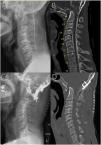

Neurosurgical management of basilar invagination (BI) has traditionally been aimed at direct cervicomedullary decompression through transoral dens resection or suboccipital decompression with supplemental instrumented fixation. Dr. Goel introduced chronic atlantoaxial dislocation (AAD) as the etiology in most cases of BI and described a technique for distracting the C1–C2 joint with interfacet spacers to achieve reduction and anatomic realignment. We present our modification to Goel’s surgical technique, in which we utilize anterior cervical discectomy (ACD) cages as C1–C2 interfacet implants. A young adult male presented to our institution with BI, cervicomedullary compression, occipitalization of C1, and Chiari 1 malformation. There was AAD of C1 over the C2 lateral masses. This reduced some with preoperative traction. He underwent successful C1–C2 interfacet joint reduction and arthrodesis with anterior cervical discectomy (ACD) cages and concomittant occiput to C2 instrumented fusion. BI can be effectively treated through reduction of AAD and by utilizing ACD cages as interfacet spacers.